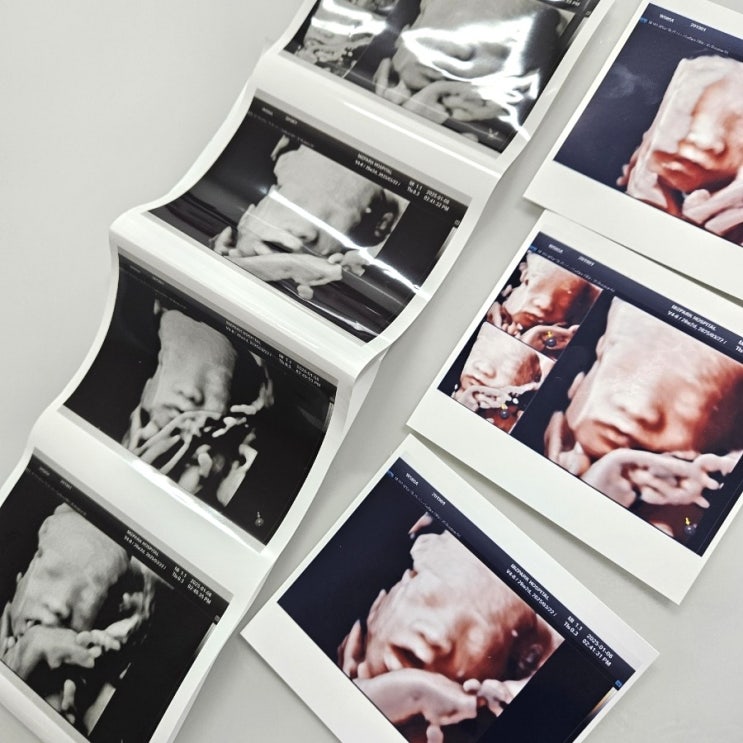

임신 28주 29주 30주 입체초음파 가격 몸무게 태동 증상

어느 덧 임신 중기를 지나 후기로 달려가고 있는 지금이에요 28주 29주 30주 이 시기에 입체초음파를 찍게 ...